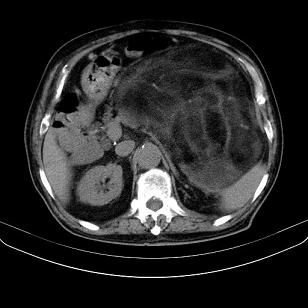

标题: CT21671:男,88岁,左上腹包块 [打印本页]

标题: CT21671:男,88岁,左上腹包块

患者因咳嗽而住院,自觉右上腹包块,无其他不适。

腹膜后高分化脂肪肉瘤

腹膜后脂肪肉瘤

腹膜生占位性病变,脂肪肉瘤可能。

脂肪肉瘤,应测ct值。

支持;后腹膜脂肪肉瘤诊断。

另肠腔扩张及液平,肠梗阻?

左侧腹膜后脂肪肉瘤。